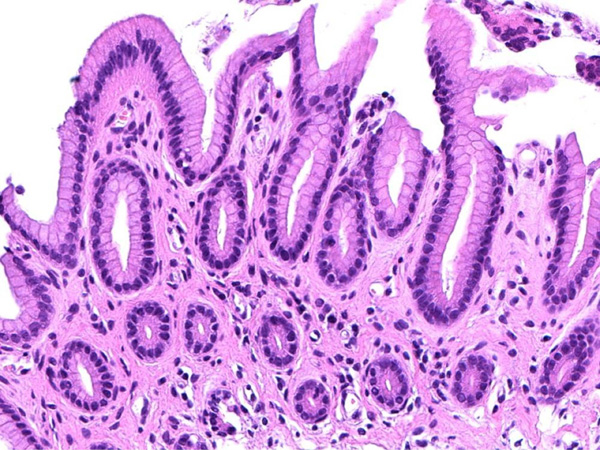

頻繁に嘔吐する猫ちゃんの精密検査依頼で内視鏡検査のご紹介がありました。内視鏡検査で胃内を検査し、数ヶ所胃粘膜を採取し病理組織検査に出しました。結果は「慢性胃炎(軽度)」とのことでした。採取粘膜ではラセン菌は認めず、リンパ球や単核細胞の浸潤を認め、検索範囲に腫瘍病変は認められませんでした。